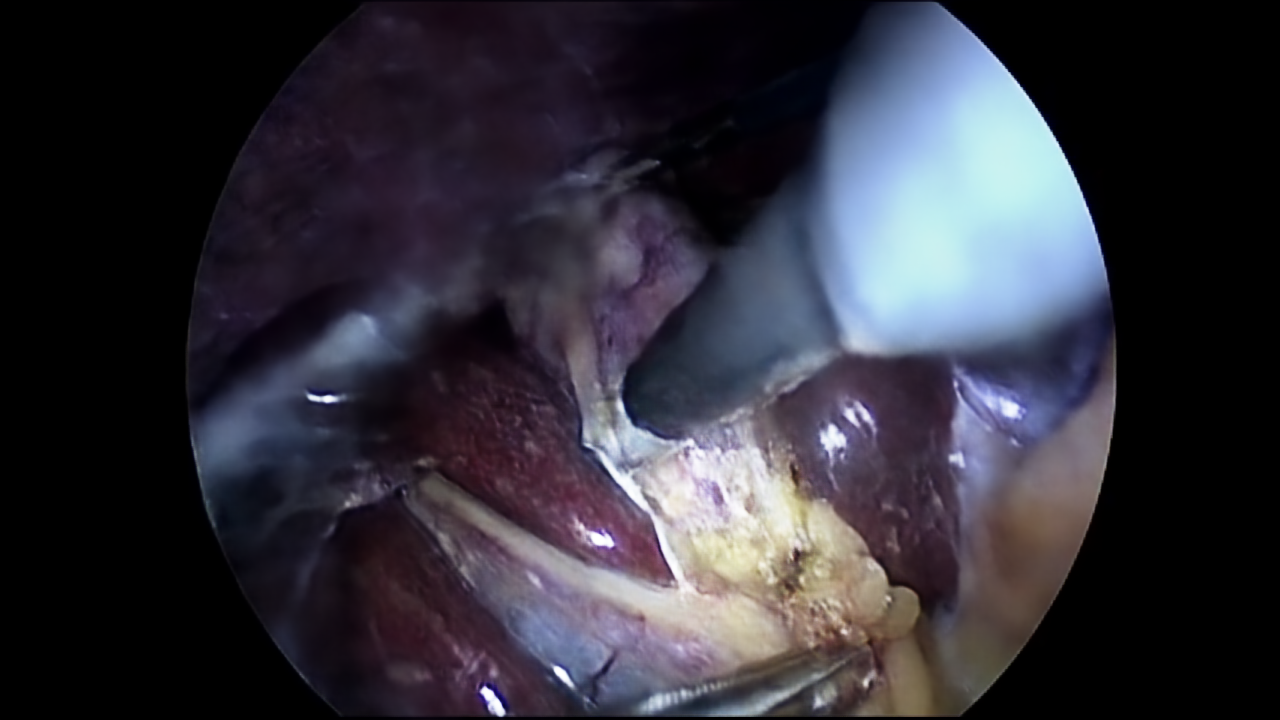

After getting NeRV to work on the “Big Bunny Dataset” we tested it on a novel dataset. We used the first 100 frames from the 13th video of the Cholec80 Dataset made by the CAMMA Research Group (Twinanda et al., 2017). This dataset is made of video of cholecystectomy surgeries.

We first tried training it for only 300 epochs with the same hyperparameters as in the section above. After around an hour of training, this resulted in a PSNR of 31.53 and a MS-SSIM of 0.9563. The visualisation for frame 10 of the NeRV-S on Cholec80 can be seen in Figure 4.

Figure 4: Ground truth (left) (Twinanda et al., 2017) and prediction (right) of NeRV-S (300 epochs) for frame 10.